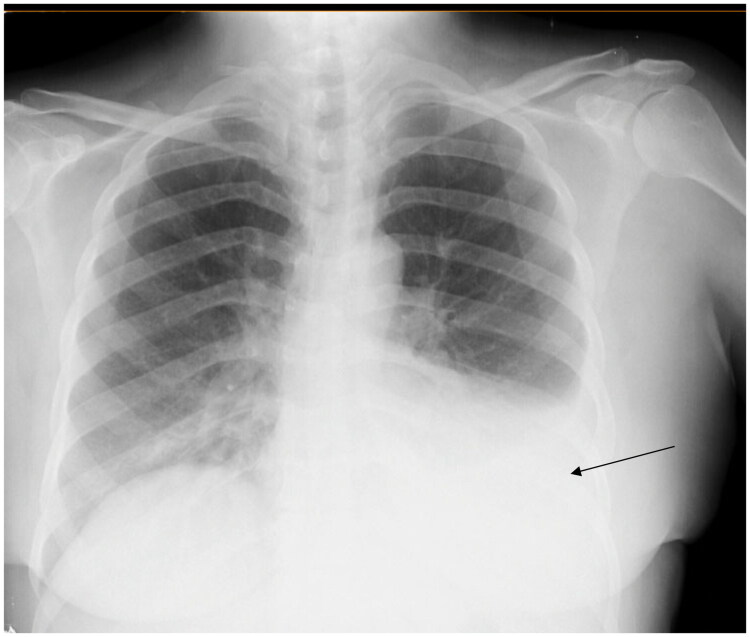

Chylothorax is an uncommon cause of pleural effusion, most often associated with malignancy, trauma, or thoracic duct obstruction. Its occurrence following SARS-CoV-2 infection is exceptional. The present case report describes a 53-year-old woman who was admitted to the pneumology department complaining of chronic dry cough with a medical history of type II diabetes and SARS-CoV-2 infection one month ago. Physical examination revealed decreased vesicular breath sounds at the left lung base. A chest X-ray revealed a left pleural effusion and thoracentesis confirmed chylothorax. This case highlights chylothorax as a rare but possible complication of COVID-19, potentially caused by inflammation and thoracic duct disruption in the absence of thrombosis. It emphasizes the importance of considering chylothorax in the differential diagnosis of unexplained pleural effusions following SARS-CoV-2 infection.